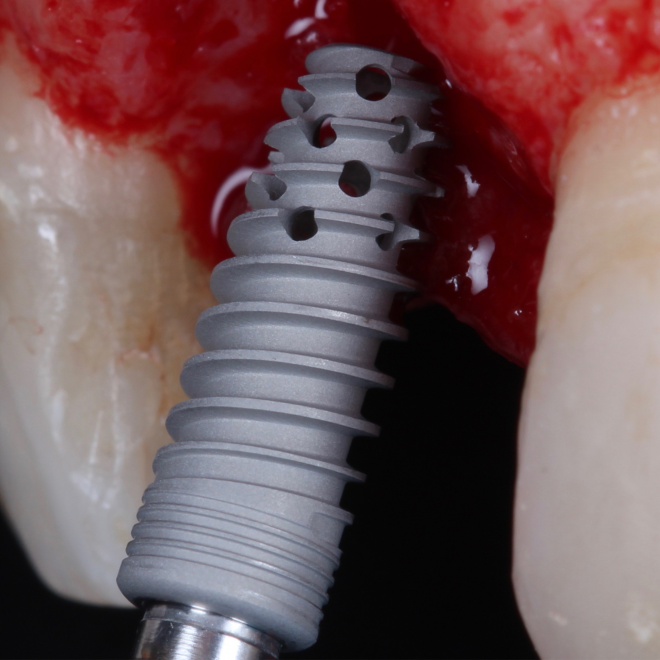

A Bionnovation possui rígidos controles na produção de seus implantes e componentes protéticos. As especificações e desenhos técnicos de cada produto possuem tolerâncias confidenciais, sendo assim, nenhum outro fabricante poderá garantir fidelidade ou compatibilidade com implantes e/ou componentes Originais Bionnovation. Os benefícios garantidos na utilização de produtos originais é a excelente adaptação entre implante e componentes.

A Bionnovation não estende sua garantia em tratamentos onde não são utilizados Implantes e Componentes Protéticos Originais.

Desde 1985 tenho colaborado com o professor Per-Ingvar Brånemark e nos últimos anos, desenvolvi, juntamente com ele e Christian Brånemark, uma nova macro geometria do ápice do implante. Está parte apical do implante tem a função de reduzir o atrito, devido a seu corte preciso, controlando o torque de inserção, coletando lascas de tecido ósseo para o interior da câmara apical.

“Since 1985 I have been collaborating with professor Per-Ingvar Brånemark and during the last years, I have, together with him and Christian Brånemark, developed a new implant tip.This part of the implant is reducing friction, due to precise cutting, reducing insertion torque and collecting bone chips inside the tip part of”